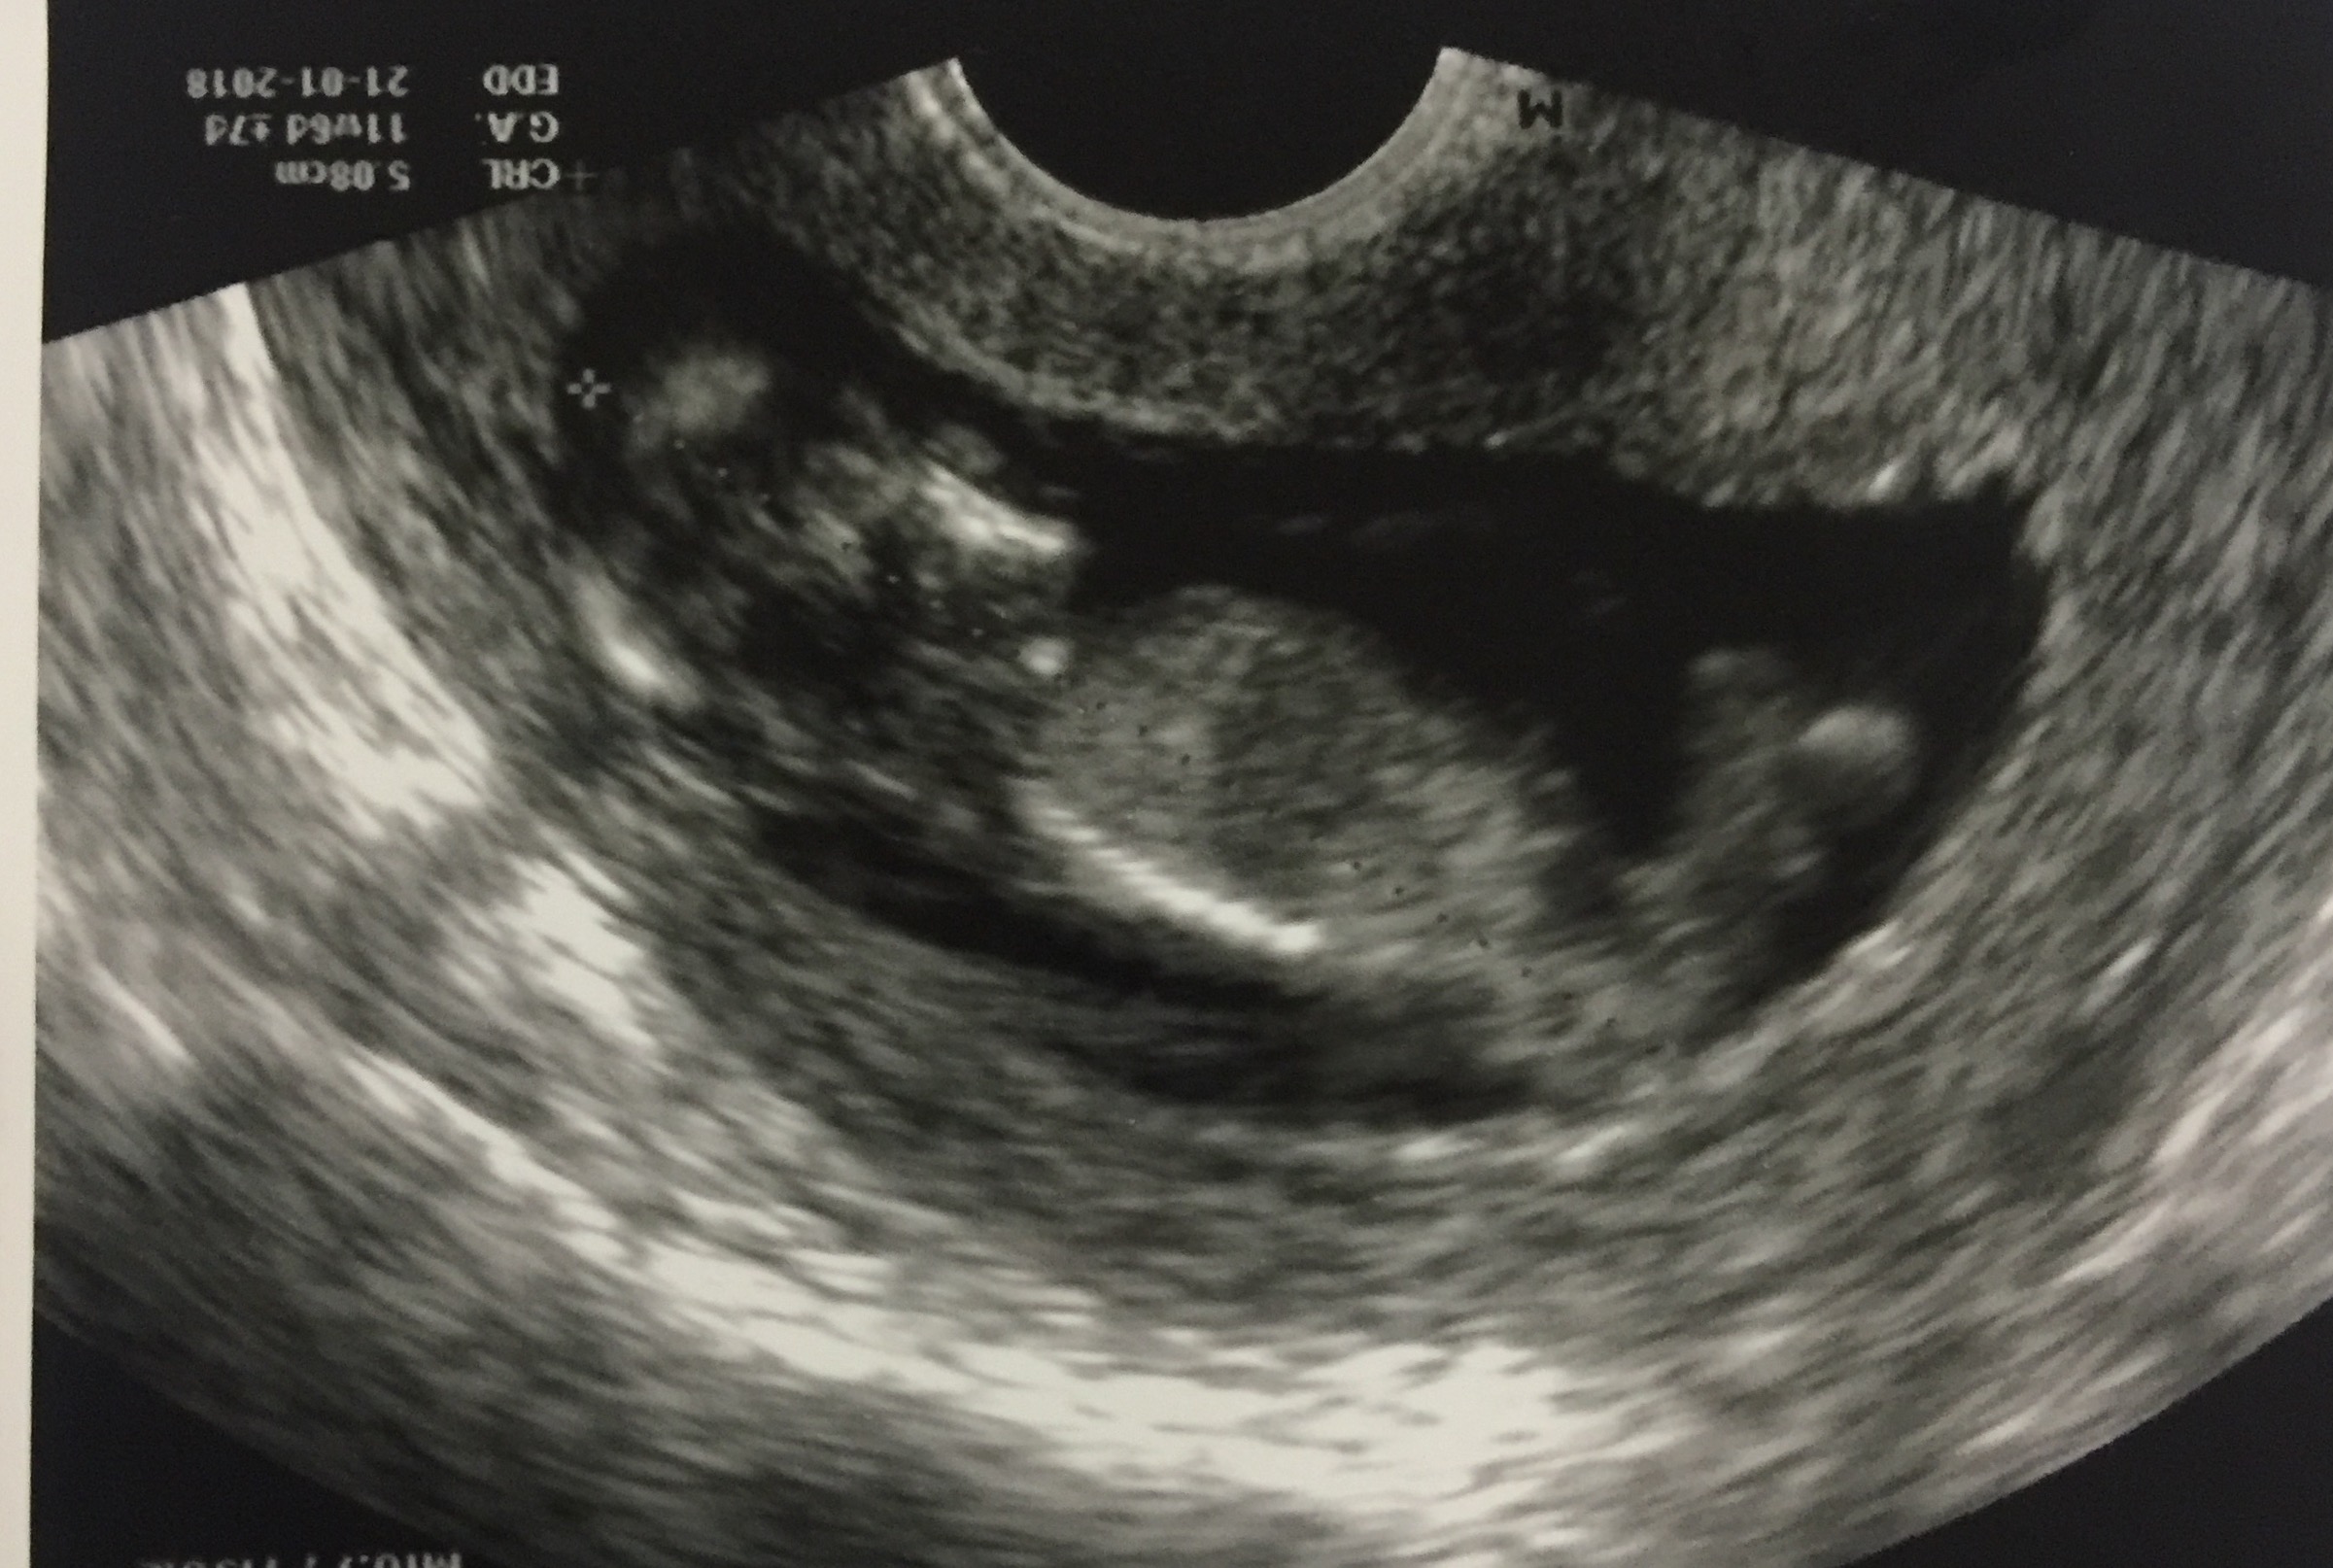

12 Week Ultrasound Gender Prediction - Male or Female (12 weeks ultrasound), How accurate is ultrasound at detecting gender?. A mother's weight also affects our ability to predict gender. Check out my designer online children's. I had my 12 week ultrasound yesterday, and my tech suggested looking up the nub… read post. You must also remember that a nub analysis before 12 weeks of pregnancy, especially for babygram can give you a reliable prediction of your baby's gender. Gender guesses following 12 week scan madeformums forum.

A theory that really works, here's how to use your scan to predict your baby's gender. Check out my designer online children's. My mom bawled her eyes out and you can hear. Biomedical papers of the medical faculty of the university palacky, olomouc, czech republic (2012) 5. You mentioned that you're 12 weeks along. But if baby is only measuring 12 weeks exactly it's still early and there is still time to change. Accuracy of sonographic fetal gender determination: We do this using the nub method!

You mentioned that you're 12 weeks along. 19 week gender scan accuracy. My baby boy in 12 week scan | gender prediction week 12 ultrasound. Ultrasound imaging performed in the 11th and 12th weeks of pregnancy for fetal gender identification identified the fetus either as a girl, a boy, or as a the sagittal sign for sonographic prediction of fetal gender in the early second trimester is described and its sensitivity and accuracy evaluated. Learn more about this theory that can predict the gender of your baby this early gender prediction theory focuses on the angle on the nub in comparison to the spine. 3,074 likes · 5 talking about this. How our 12 week ultrasound showed baby's gender! I had my 12 week ultrasound yesterday, and my tech suggested looking up the nub… read post. Early baby gender predictor explained 2019. My mom bawled her eyes out and you can hear. Would love some guesses on what it is :)&nb. Check out our 12 week ultrasound, where we find out the gender of our baby! 12 week ultrasound gender ultrasound gender prediction pregnancy gender reveal pregnancy goals pregnancy photos baby photos 12 week scan how to 'predict' baby's gender from an early ultrasound.

Had our 12 week ultrasound today!! I just had my 20 week u/s and they said it was a girl. Nub method has very high accuracy when measuring angle of nub compared to spine! He is measuring at 5.5 pounds. I have two boy's, so i'm skeptical. 12 week ultrasound gender ultrasound gender prediction pregnancy gender reveal pregnancy goals pregnancy photos baby photos 12 week scan how to 'predict' baby's gender from an early ultrasound. How our 12 week ultrasound showed baby's gender! You must also remember that a nub analysis before 12 weeks of pregnancy, especially for babygram can give you a reliable prediction of your baby's gender.